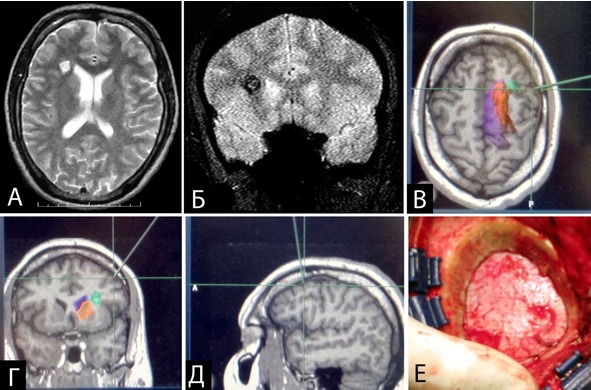

Нейронавигация по данным предоперационного пакета МРТ использовалась в 22 случаях. Чаще методику применяли для планирования доступа к небольшим глубинно расположенным каверномам (средний размер каверномы составил 1,6±1,4 см, рисунок 26). Для удаления каверномы во всех 22 случаях выполнена одна энцефалотомия. Метод позволил найти каверному сразу в 20 наблюдениях. В двух случаях возникли затруднения при поиске каверномы в связи со смещением структур на расстояние до одного сантиметра. Во всех случаях выполнена сравнительно небольшая краниотомия (не более 4 см). Минимальный размер каверномы, найденной при помощи нейронавигации, составил 0,3 см. Метод использовали на двух повторных операциях после неудачной попытки найти каверному. В обоих случаях кавернома легко найдена и удалена. Метод удобен для планирования доступа и первичного поиска каверномы, однако его использование для определения объема резекции измененного мозгового вещества в дальнейшем невозможно в связи со значительным смещением близлежащих структур после удаления мальформации.

Рисунок 26. Пример удаления небольшой каверномы (0,5 см в диаметре) правой лобной доли с использованием МРТ-навигации. А – МРТ в Т2 режиме, аксиальная проекция, Б – МРТ в Т2* режиме, фронтальная проекция. В, Г, Д – реконструированные по данным предоперационного пакета МРТ данные для МРТ-навигации, планирование доступа. Зеленым цветом отмечена кавернома, оранжевым – базальные ядра, фиолетовым – боковой желудочек. Е – небольшая (2,5 см в диаметре) трепанация для доступа к каверноме.